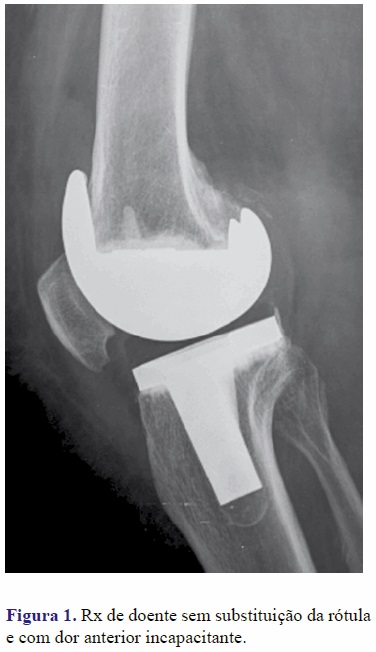

Não foi documentado nenhum caso de revisão cirúrgica por infecção. No grupo B 2 doentes foram reintervencionados para realinhamento do aparelho extensor e 5 reintervencionados para substituição da rótula (Figuras 1 e 2). Nenhum doente do Grupo A foi revisto até à data do estudo.